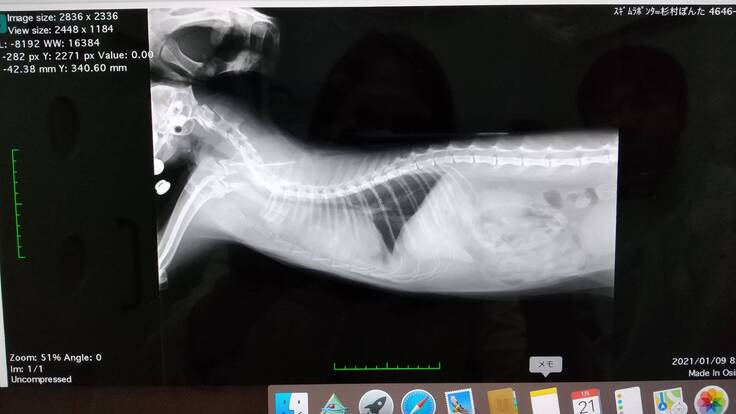

1年くらいすごく元気に楽しく暮らしていたのですが、2020年12月29日の夜中に体調が悪そうにしていました。年末だったこともあり、掛かりつけの病院がお休みだったので、診てもらえる別の病院を探しました。2020年12月30日急にぽんちゃんの呼吸が荒くなり苦しそうにしていて、朝一番で受診しました。胸水が溜まってて危ない状態でした。レントゲンを撮ったら肺が真っ白で300mlくらい水が溜まっていてぬいてもらいました。その日はICUに入って退院になりました。胸水が溜まった原因がFIP(猫伝染性腹膜炎)か悪性リンパ腫と言われました。年末休みに入っていたので検査センターに出す事ができずステロイドの内服薬をもらいました。

2021年1月7日胸水が溜まってないかレントゲンを撮ってもらい少し溜まっているが、抜くまでにはなりませんでした。胸のレントゲンを見せてもらったら通常の子より胸のほとんどが真っ白で治療をしないと後2ヶ月も生きられないと言われました。

初めての抗がん剤治療1月8日最初の抗がん剤治療のときのレントゲン写真です。真ん中の白くなっている部分が腫瘍です。この日からぽんちゃんの抗がん剤治療が始まりました。2ヶ月間は2種類の抗がん剤を週に1回投与します。初めての抗がん剤治療なので1日入院になり、胸水も溜まっていて溜まると呼吸困難になるので抜いてもらいました。2種類の抗がん剤治療をしたので胃と腸と骨髄に副作用が強く出てしまい、食欲が全くなくなってしまいましたので、3日間点滴に通いました。1回目の抗がん剤治療の経過です。

毛は抜けてしまった部分はまだ全然生えてきてませんが、2ヶ月もたないと宣告されていたぽんちゃんも3月中旬現在も生きている事がすごく嬉しいです。レントゲンの写真を見てもわかるように最初の頃の、白かった胸の部分もかなり良くなってきてます(^-^)